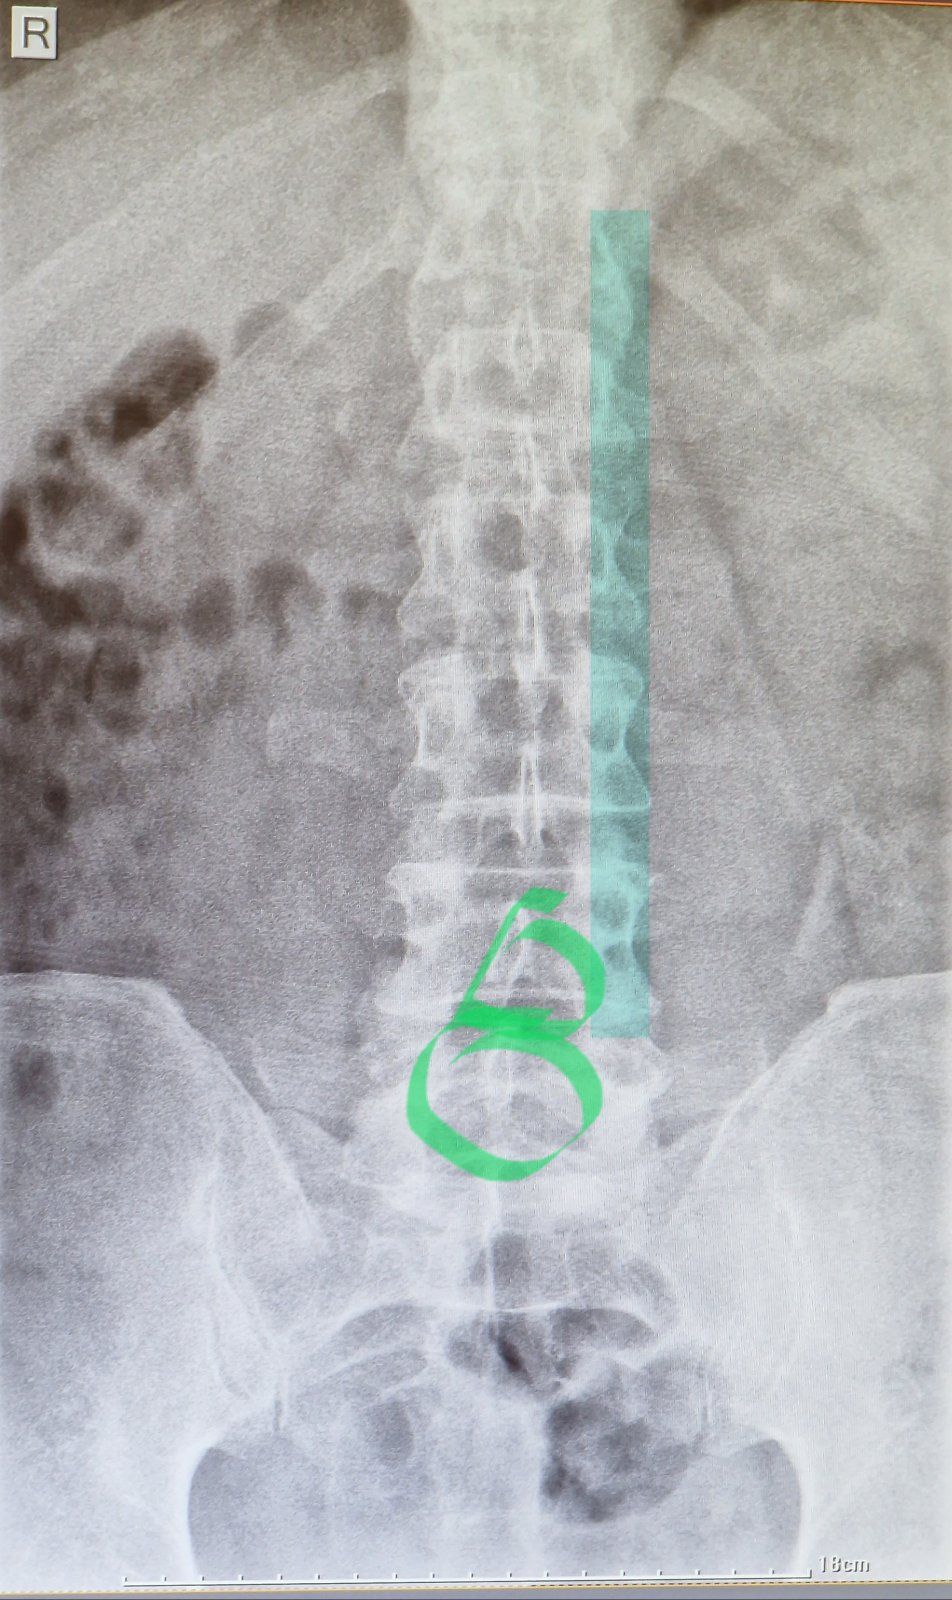

Die Polyklinik der größeren Stadt Izki liegt heute morgen direkt an unserer Route. Da legen wir doch mal einen kurzen Zwischenstopp ein, investieren zwanzig Minuten und fünf omanische Rial und knipsen ein bisserl in mich rein. Eine Untersuchung findet ansonsten eher nicht statt: Der Doc jagt mir ne Schmerzspritze in den Rücken, drückt mit ein paar chinesische Voltaren-Generica in die Hand und meint nach fünf Sekunden Röntgenbildblick nur: Alles OK.

Von einer deutschen Spezialistin bekomme ich allerdings trotz unmöglicher Qualität eines Handyfotos vom Krankenhaus-Bildschirm eine andere Diagnose. Und was meint ihr so? Sofort heimfliegen und unters Messer? Strandurlaub statt biken? Weiterfahren und Zähne zusammenbeißen?

Die deutsche Spezialistin hat im Zweifelshall Recht. Bin nur "Viehdoktor" und habe wenig Erfahrung im Beurteilen von Röntgenbildern der Wirbelsäule.Schon gar nicht bei Homo sapiens. Aber auf dem Bild scheinen eine Wirbel nicht mehr schön gerade ausgerichtet zu sein. Meine, das anhand der Wirbelfortsätze zu erkennen. Habe das mal auf dem Bild markiert. Vergleiche die türkisen "Textmarker-Wirbel" mit den eingekreisten Wirbeln. Einfach mal die Ausrichtung der Wirbelfortsätze mittig ("elliptische Schiffchen" in der Mittte) vergleichen.

Kann mich natürlich komplett irren und das hier ist ausdrücklich KEINE Diagnose. Ich würde selbst heimfahren oder in der erweiterten Region zu einem Spezialisten gehen (VAE?).

Anyway... die Remote-Diagnose der Chef-Radiologin von daheim: Querfortsatz rechts bei LWK 3 auffällig, fraglich auch LWK 4. Konsequenz: Keine.

Nach kaum ner halben Stunde sind wir schon wieder aus aus dem Krankenhaus von Izki: Röntgenbild machen ging flott wie's Brezl backen: Wartezeiten keine, Kosten keine, Diagnose auch keine. Die kommt wenig später aus Deutschland: "Querfortsatz rechts bei LWK 3 auffällig, fraglich auch LWK 4". Könnte also schon was angeknaxt sein, sofern man das anhand von abfotografierten Krankenhaus-Bildschirmen noch beurteilen kann. Die Schmerzen passen jedenfalls irgendwie dazu. Egal, nix besonders ernstes, damit bin ich erst mal zufrieden. Ein MRT such ich mir jetzt aber nicht auch noch, irgendwann muss man die Kirche einfach im Dorf lassen. Der Milz geht's prima, hat sie mich gerade wissen lassen.